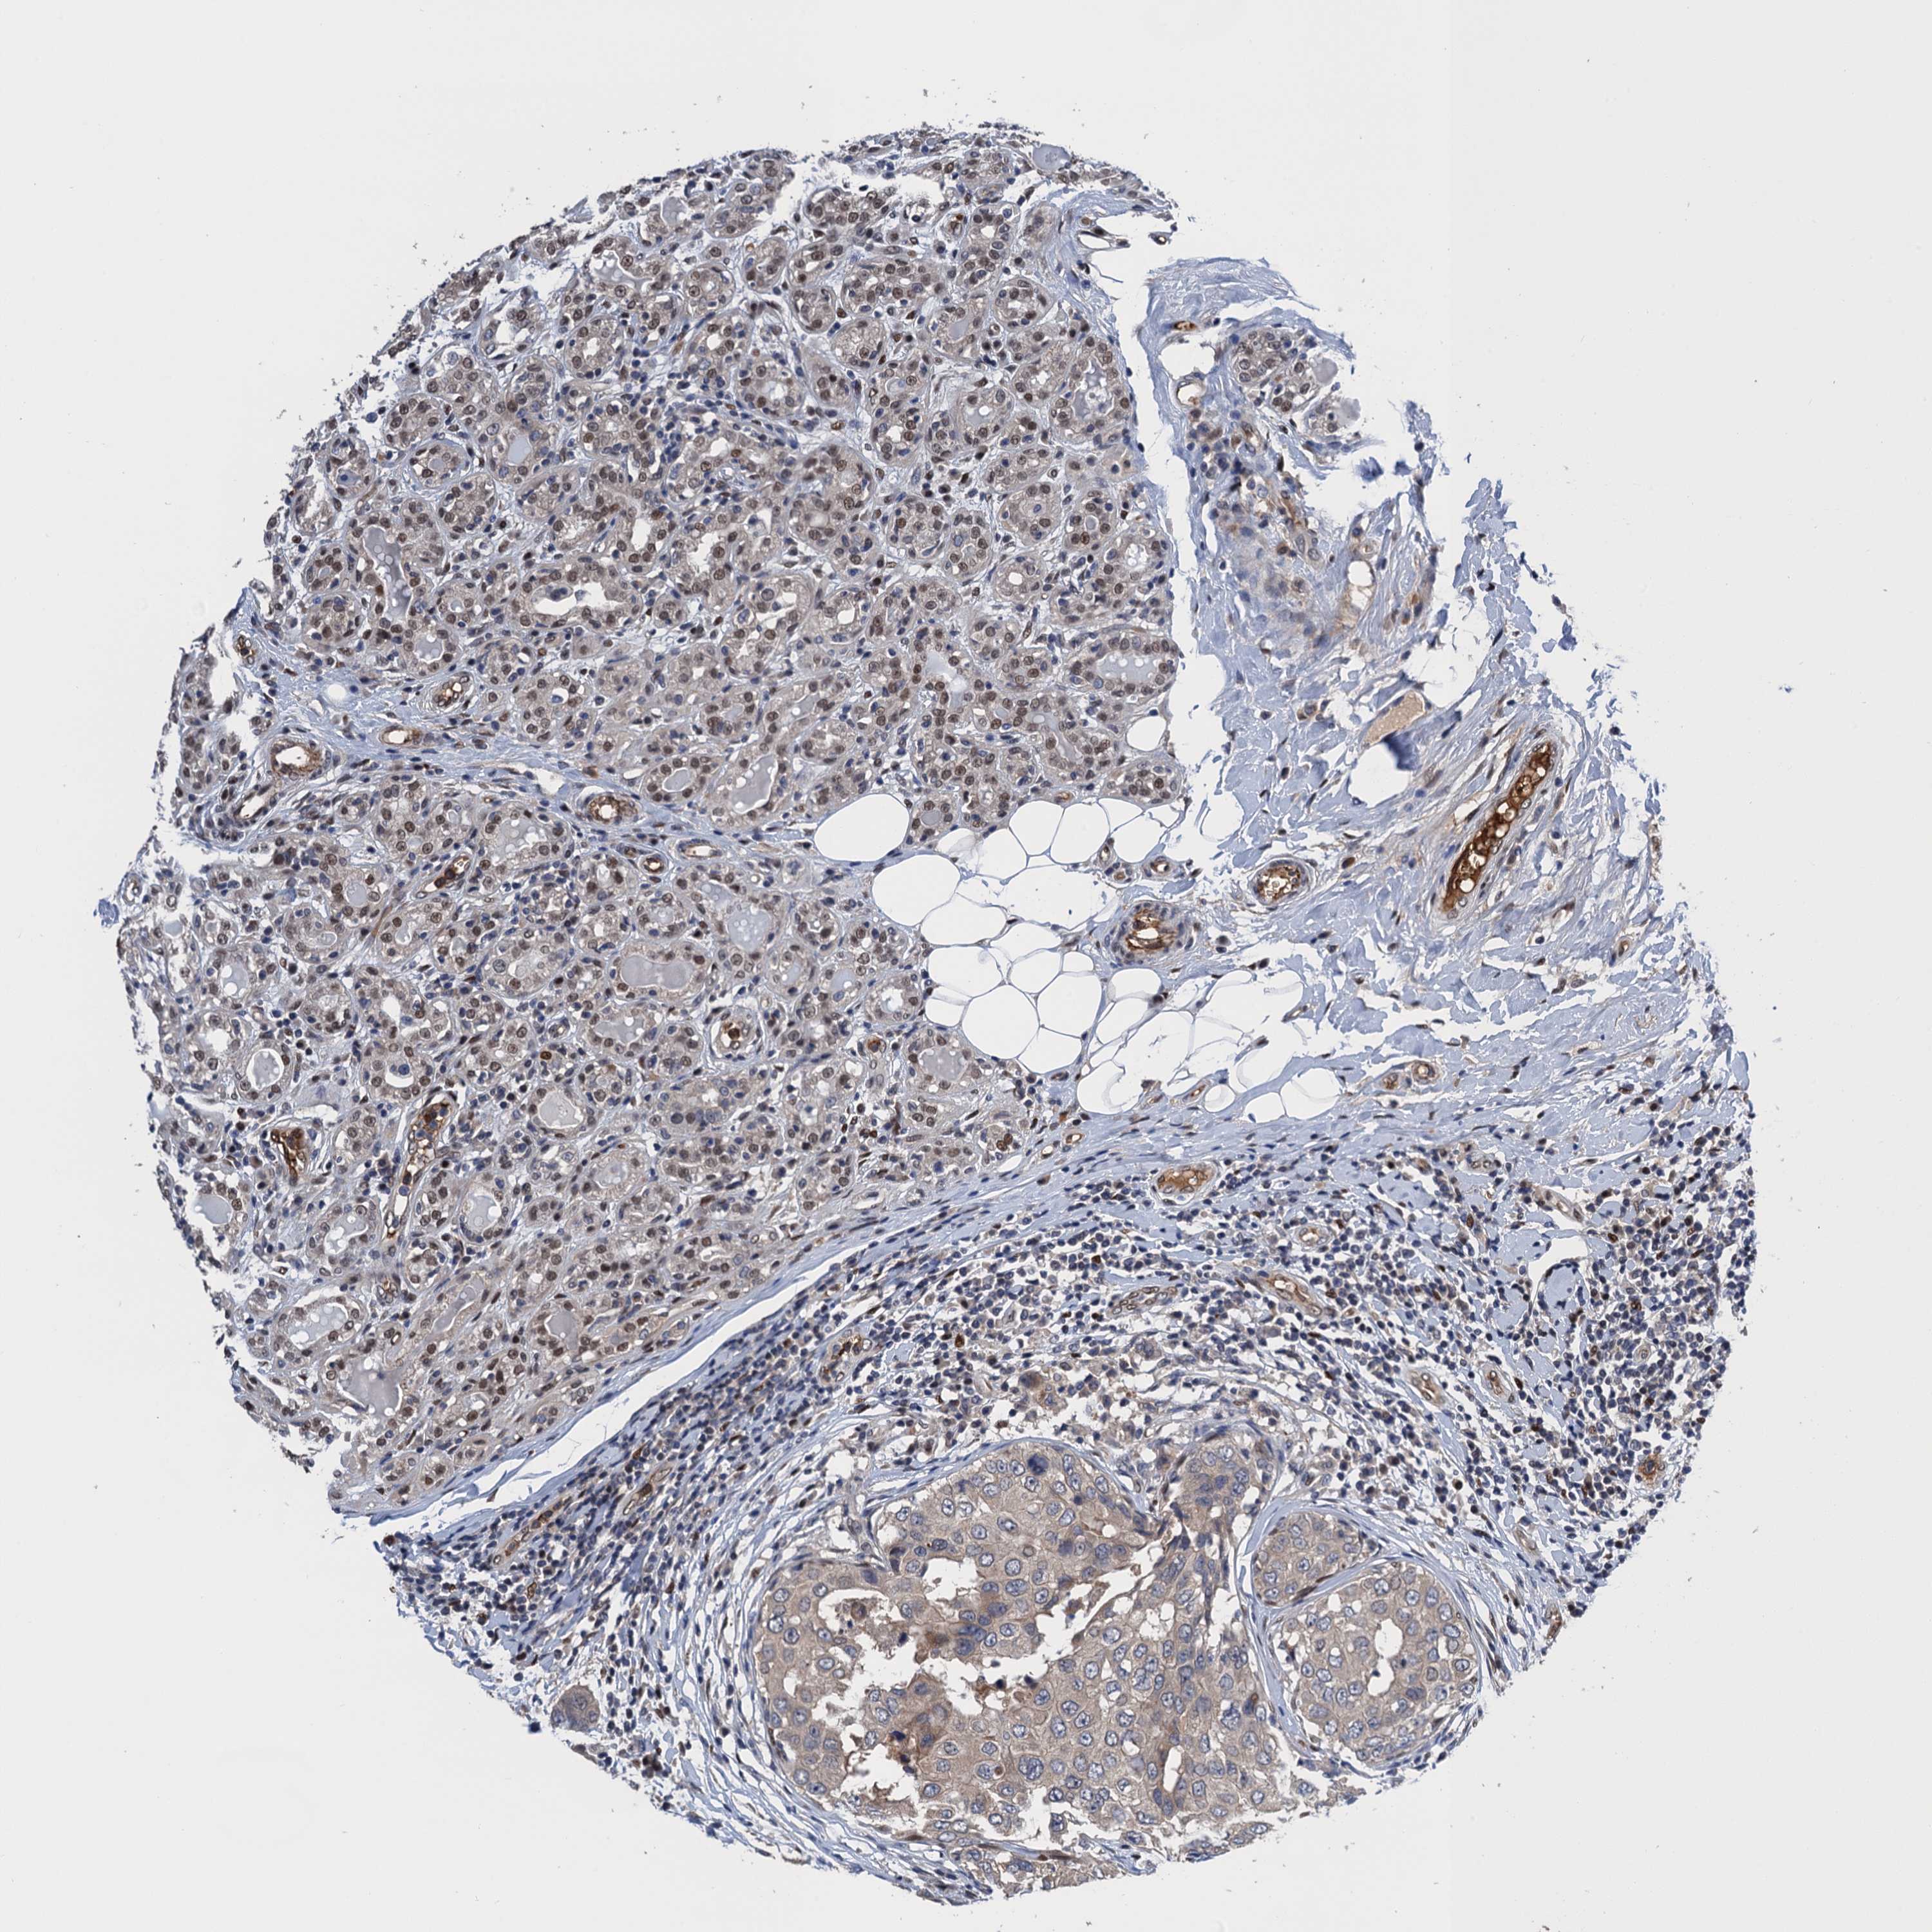

CANCER BREAST CANCER Show tissue menu

BRCA TCGA BRCA VALIDATION PROTEIN EXPRESSION

ANTIBODIES

AND

VALIDATION